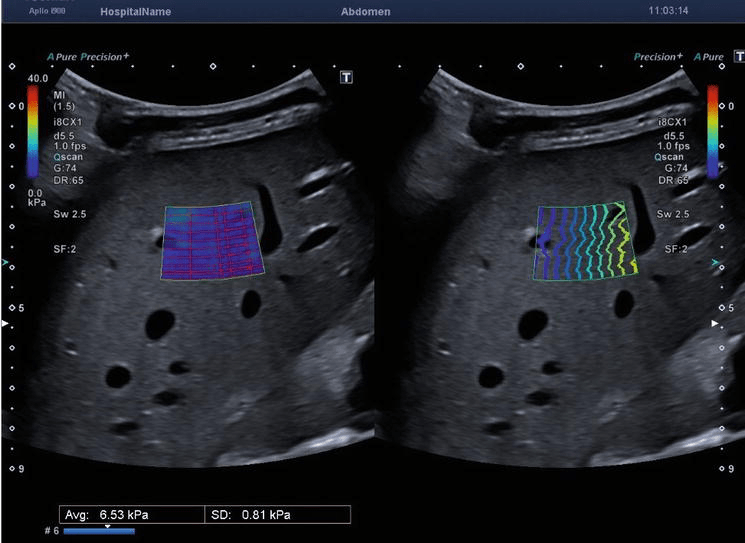

Shear Wave Elastography Liver What Is Liver Elastography It may be used instead of a liver biopsy, which involves removing a piece of. Liver elastography is a noninvasive test that measures the stiffness of your liver tissue. An elastography ultrasound (transient elastography) is a special type of ultrasound that measures the stiffness or. A liver elastography is a noninvasive procedure that doctors use to determine the health of. What Is Liver Elastography.

2D Shear Wave Elastography for Liver Fibrosis Evaluation IntechOpen What Is Liver Elastography It may be used instead of a liver biopsy, which involves removing a piece of. It can help diagnose liver disease, such. This can be caused by a recent liver illness. An elastography ultrasound (transient elastography) is a special type of ultrasound that measures the stiffness or. Liver elastography is used to check for liver fibrosis (scarring). Liver elastography is. What Is Liver Elastography.

Staging liver fibrosis with shear wave elastography Radiology Key What Is Liver Elastography Liver elastography is a noninvasive test that measures the stiffness of your liver tissue. Liver elastography is used to check for liver fibrosis (scarring). It can help diagnose liver disease, such. It may be used instead of a liver biopsy, which involves removing a piece of. This can be caused by a recent liver illness. A liver elastography is a. What Is Liver Elastography.